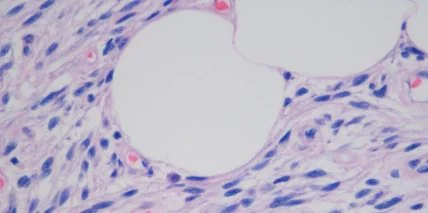

В основе новой разработки - микроскоп, микропипетка и лазер. С помощью такого механизма можно будет извлекать и возвращать в организм митохондрии.

Было выяснено, что многие митохондрии могут мутировать и вызывать смертельные заболевания. Новая же разработка позволит редактировать ДНК и таким образом спасать жизнь человека.